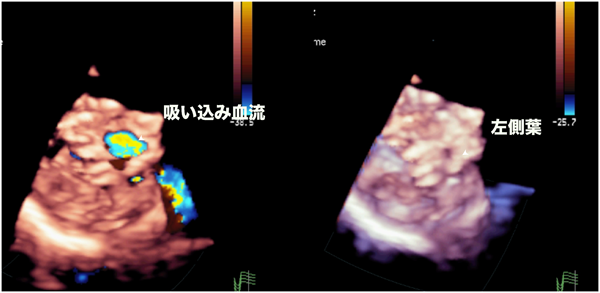

2024年 お歳暮・冬ギフト特集 実践3D心エコー図法 医学一般